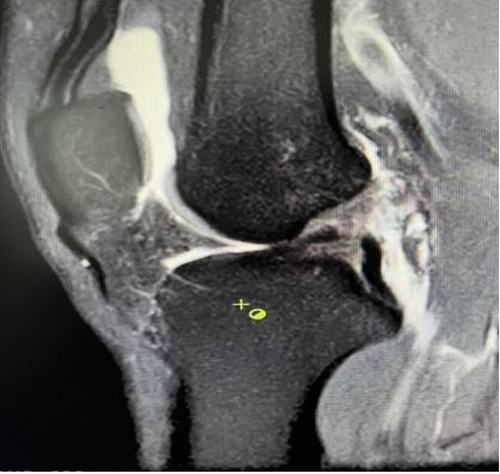

膝關節韌帶損傷磁共振

我院骨科三病區近期收治了4名膝關節交叉韌帶損傷患者。25歲的齊先生,因打籃球時不慎扭傷左膝,致右膝腫痛,遂來我院治療;30歲趙先生酷愛足球,扭傷右膝關節來我院就診;50歲的張先生、42歲劉先生因騎車滑倒摔傷、膝關節腫痛不適、活動受限,收治入院。骨科三病區李鵬主任團隊詳細查體以及完善影像學檢查后進行診斷:幾位患者共同診斷均有“前交叉韌帶損傷”,不同程度合并有“半月板損傷”、“股骨軟骨損傷”、“內側副韌帶斷裂”。